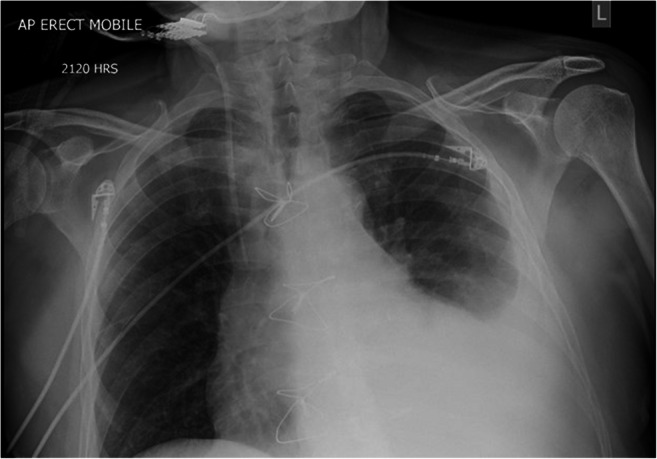

On postoperative day four, the patient was transferred back to the ICU due to increasing respiratory requirements, in what appeared to be a COPD exacerbation. The patient initially improved with medical therapy. On postoperative day six, the patient’s sternum was noted to be unstable on physical examination, with no evidence of sternal wound infection. Chest X-ray revealed a single fractured sternal wire (Fig. 1). The patient was scheduled for repair of his sternal dehiscence the following day. While awaiting reoperation, the patient was ambulating with minimal assistance and developed sudden-onset shortness of breath, became pale with cool extremities, and had bleeding from his sternal incision. Urgent repeat chest X-ray showed a new left pleural effusion (Fig. 2). A bedside echocardiogram was immediately ordered to rapidly assess the new bleeding. The echocardiogram showed a significant pericardial effusion. The patient was resuscitated with fluids, received two units of packed red blood cells (pRBC) for significant blood loss, and was started on norepinephrine for hemodynamic support. He was then taken emergently to the operating room for re-exploration. On re-exploration, there were large mediastinal clots. Contrary to the X-ray findings, all sternal wires were found to be fractured with a laceration injury to the free wall of the RV. The laceration was successfully repaired using a pledgeted 4-0 polypropylene suture. The pericardium was left open and the sternum was closed using the same figure-of-8 method, with 6 sternal wires and was reinforced with 4 parasternal wires. The patient was transfused with a single unit of pRBC intra-operatively and was transferred to the ICU with stable hemodynamics. He was successfully extubated the next day and discharged home 15 days after his initial procedure.

Fig. 2.

Left pleural and pericardial effusions seen on chest X-ray